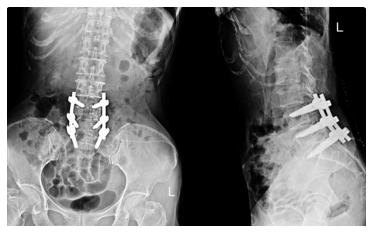

In recent years, there has been a steady and disquieting rise in the number of spinal fusion procedures being recommended and performed - many of which, upon rigorous examination, fall short of the stringent clinical thresholds that once defined the necessity of such an intervention.11,16 Fusion, while undeniably valuable and at times indispensable in cases of demonstrable mechanical instability (such as in spondylolisthesis with slippage, gross segmental hypermobility, or spinal deformity correction), is increasingly being applied in settings where the evidence of benefit is ambiguous or entirely absent (Figure 5).20–22

Figure 5 Typical lumbo-sacral arthrodesis.

• Heightened likelihood of revision surgery, particularly in multilevel constructs, elderly patients, or those with poor bone quality or pseudarthrosis (Figure 6).22,28

Figure 6 Two illustrative examples of “Adjacent Segment Disease”.